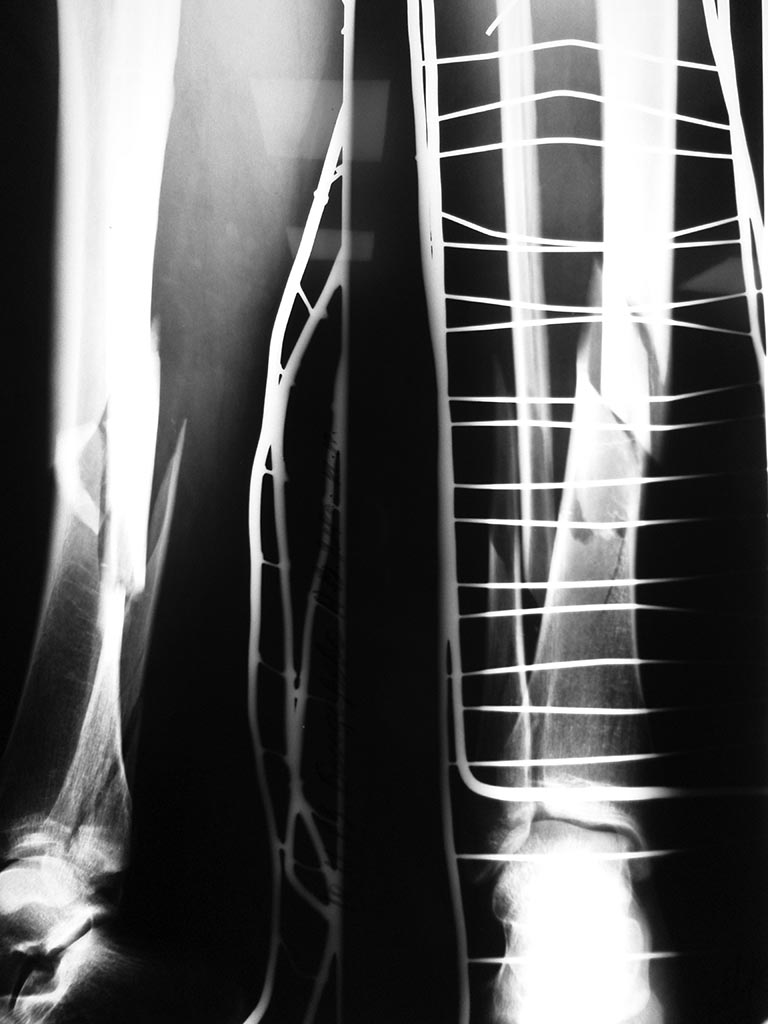

Представляю вашему вниманию случай Ж, 24 лет, не курит, оступилась на

скользких ступенях и подвернула ногу,уложена ССВ,кожа спокойная,

сосудистых и неврологических расстройств нет, проводится

предоперационная подготовка. Ваше мнение каким образом синтезировать

малоберцовую кость. прошу обратить внимание, что вовлечена наружная лодыжка.